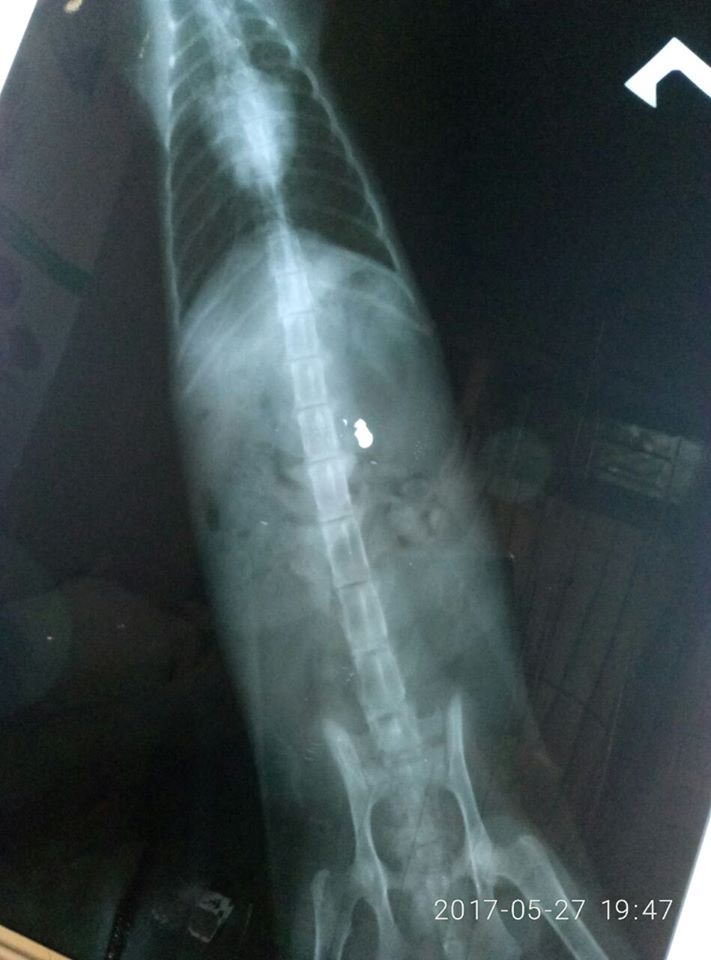

Кошка была доставлена в ветеринарную клинику Красный лис. Огромное спасибо врачам, которые ждали нас до ночи и оказали квалифицированную помощь: Было откачано 700 мл мочи из - за атонии мочевого пузыря, сделан рентген и компьютерная томограмма.

Исследования показали, что в результате выстрела был перебит позвонок, затронут спиной мозг (она никогда не будет ходить). Но сегодня под угрозой жизнь! Жизнь маленькой Шурочки! И если не сделать сложную операцию по удалению осколков от пули и острых осколков позвонка, все это будет приносить мучительную боль.